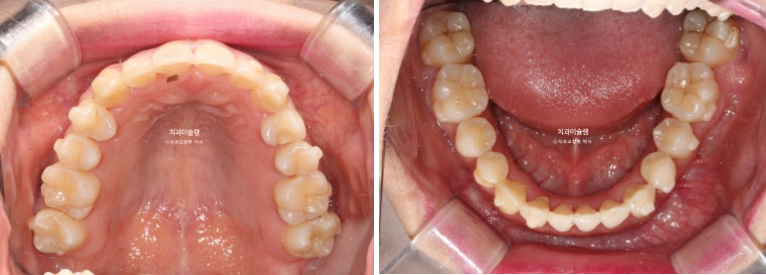

23.08~25.10

상악 제2대구치 발치공간을 이용하여 송곳니 덧니를 배열했습니다.

사랑니는 발치한 두 번째 큰어금니 자리를 잘 채워주고 있습니다.

하악 사랑니 공간을 이용하여 덧니를 배열했습니다.